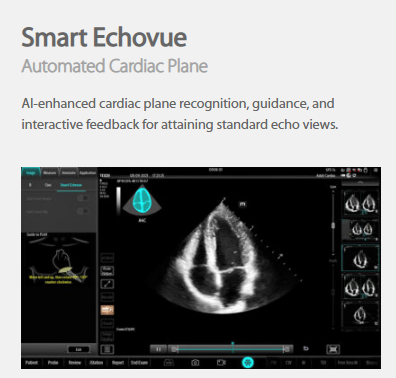

The technology-rich TE X Ultrasound System gives clinicians access to market-leading artificial intelligence (AI)-powered Smart Tools, an ergonomically designed system, and proprietary software-based beamformer Zone Sonography Technology+ (ZST+). By incorporating these elements, the TE X Ultrasound System provides access to advanced diagnostic data, the ability to adapt to the various clinical scenarios at point of care, and best-in-class imaging to help them provide a higher standard of care.